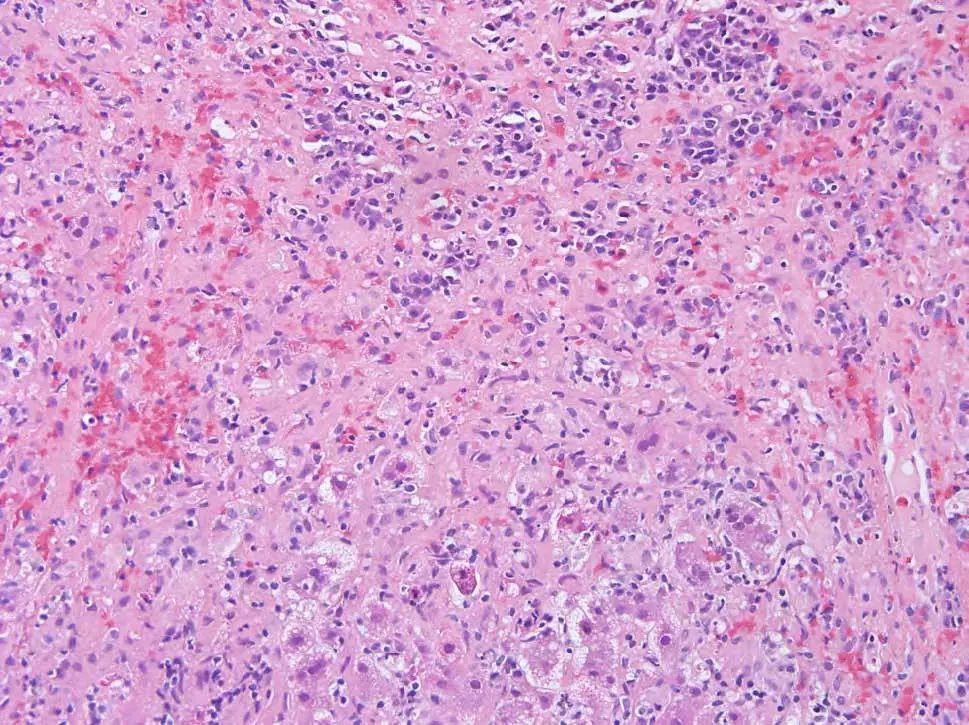

行肝活检,病理检查显示局灶性桥接或融合性坏死,伴有肝细胞脱落、凋亡(图2),易见成片浆细胞(图3)。

图2 患者病理切片示局灶性桥接或融合性坏死

可见肝细胞玫瑰花环样结构(图4),淋巴浆细胞浸润和穿入现象(炎症活动时可见一个淋巴细胞进入和穿越另一个大淋巴细胞)(图5),但没有发现病毒包涵体,水痘-带状疱疹病毒(VZV)的PCR结果为阴性。

病理诊断提示AIH。